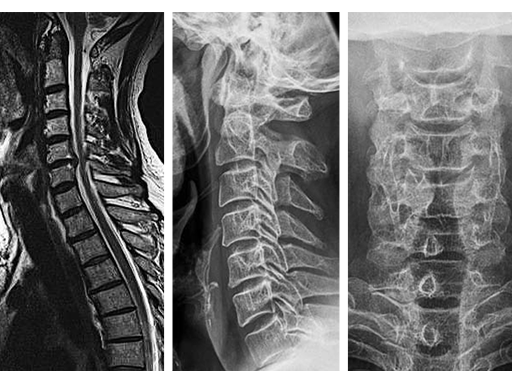

Case: Man with neck and arm pain

A 50-yr-old man presented with a 4 month history of neck and arm pain on the right side. Repeated trials of conservative treatment, including imageguided injections, had not led to a significant relief of symptoms. Clinical examination showed a C6 radiculopathy on the right side with pain, hypoaesthesia, and a slight biceps weakness.

The MRI (Fig 1a) showed a disk herniation C5/6 medial and paramedian right-sided. The preop xrays (Fig.1b-c) showed a slight narrowing of the disc space at C5/6. The segment was still mobile.